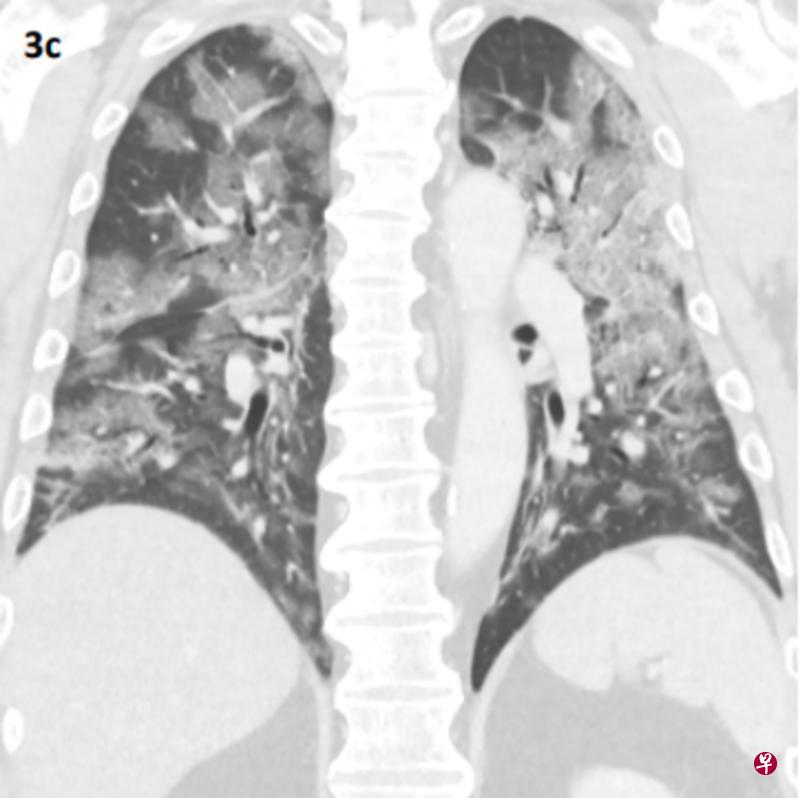

本地医疗报告首次公开2019冠状病毒疾病病患的肺部扫描影像,显示患者肺部出现形同“碎石路”的不规则阴影。

报告首次公开本地一名53岁冠病病患的胸部X光和电脑断层扫描(又称CT扫描)影像,显示他入院初期肺部出现磨玻璃影(ground-glass opacities),部分阴影更遮盖了血管。此外,病患肺部的小叶间隔增厚,形成网状细线,重叠于磨玻璃影上看似“碎石路”(crazy paving)。